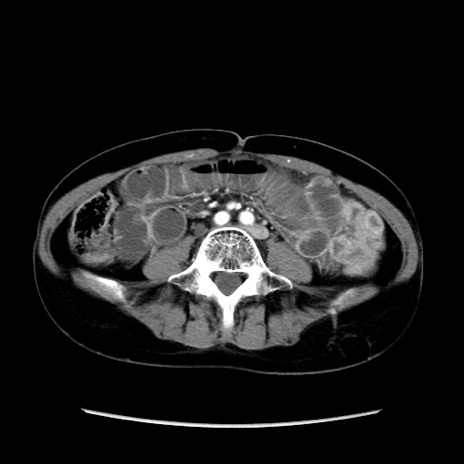

冠状断像

【症例】40歳代 女性

【主訴】上腹部痛、嘔気・嘔吐

【現病歴】約9時間前頃から急に上腹部痛、嘔気、嘔吐が出現。改善しないため救急要請。

【既往歴】子宮頚癌(広汎子宮全摘術、放射線療法)、腸閉塞

【身体所見】腹部:平坦、軟、腸雑音亢進、上腹部を中心に腹部全体に圧痛あり。

【データ】WBC 8400、CRP 0.03